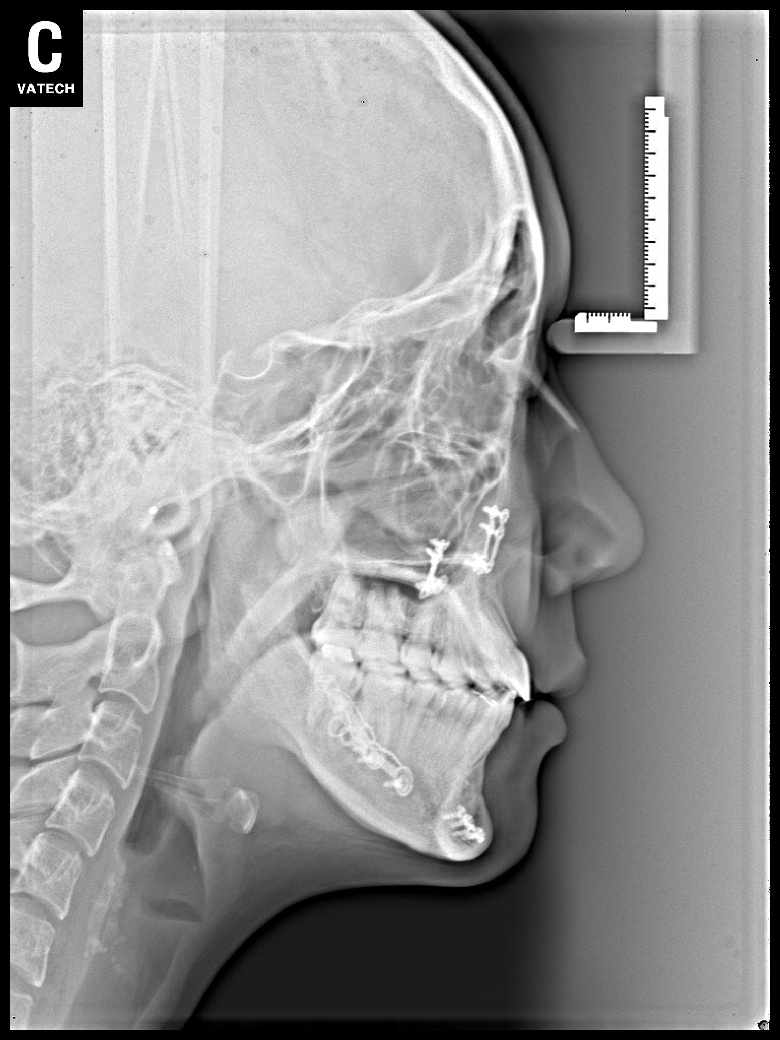

치료 전 사진입니다.